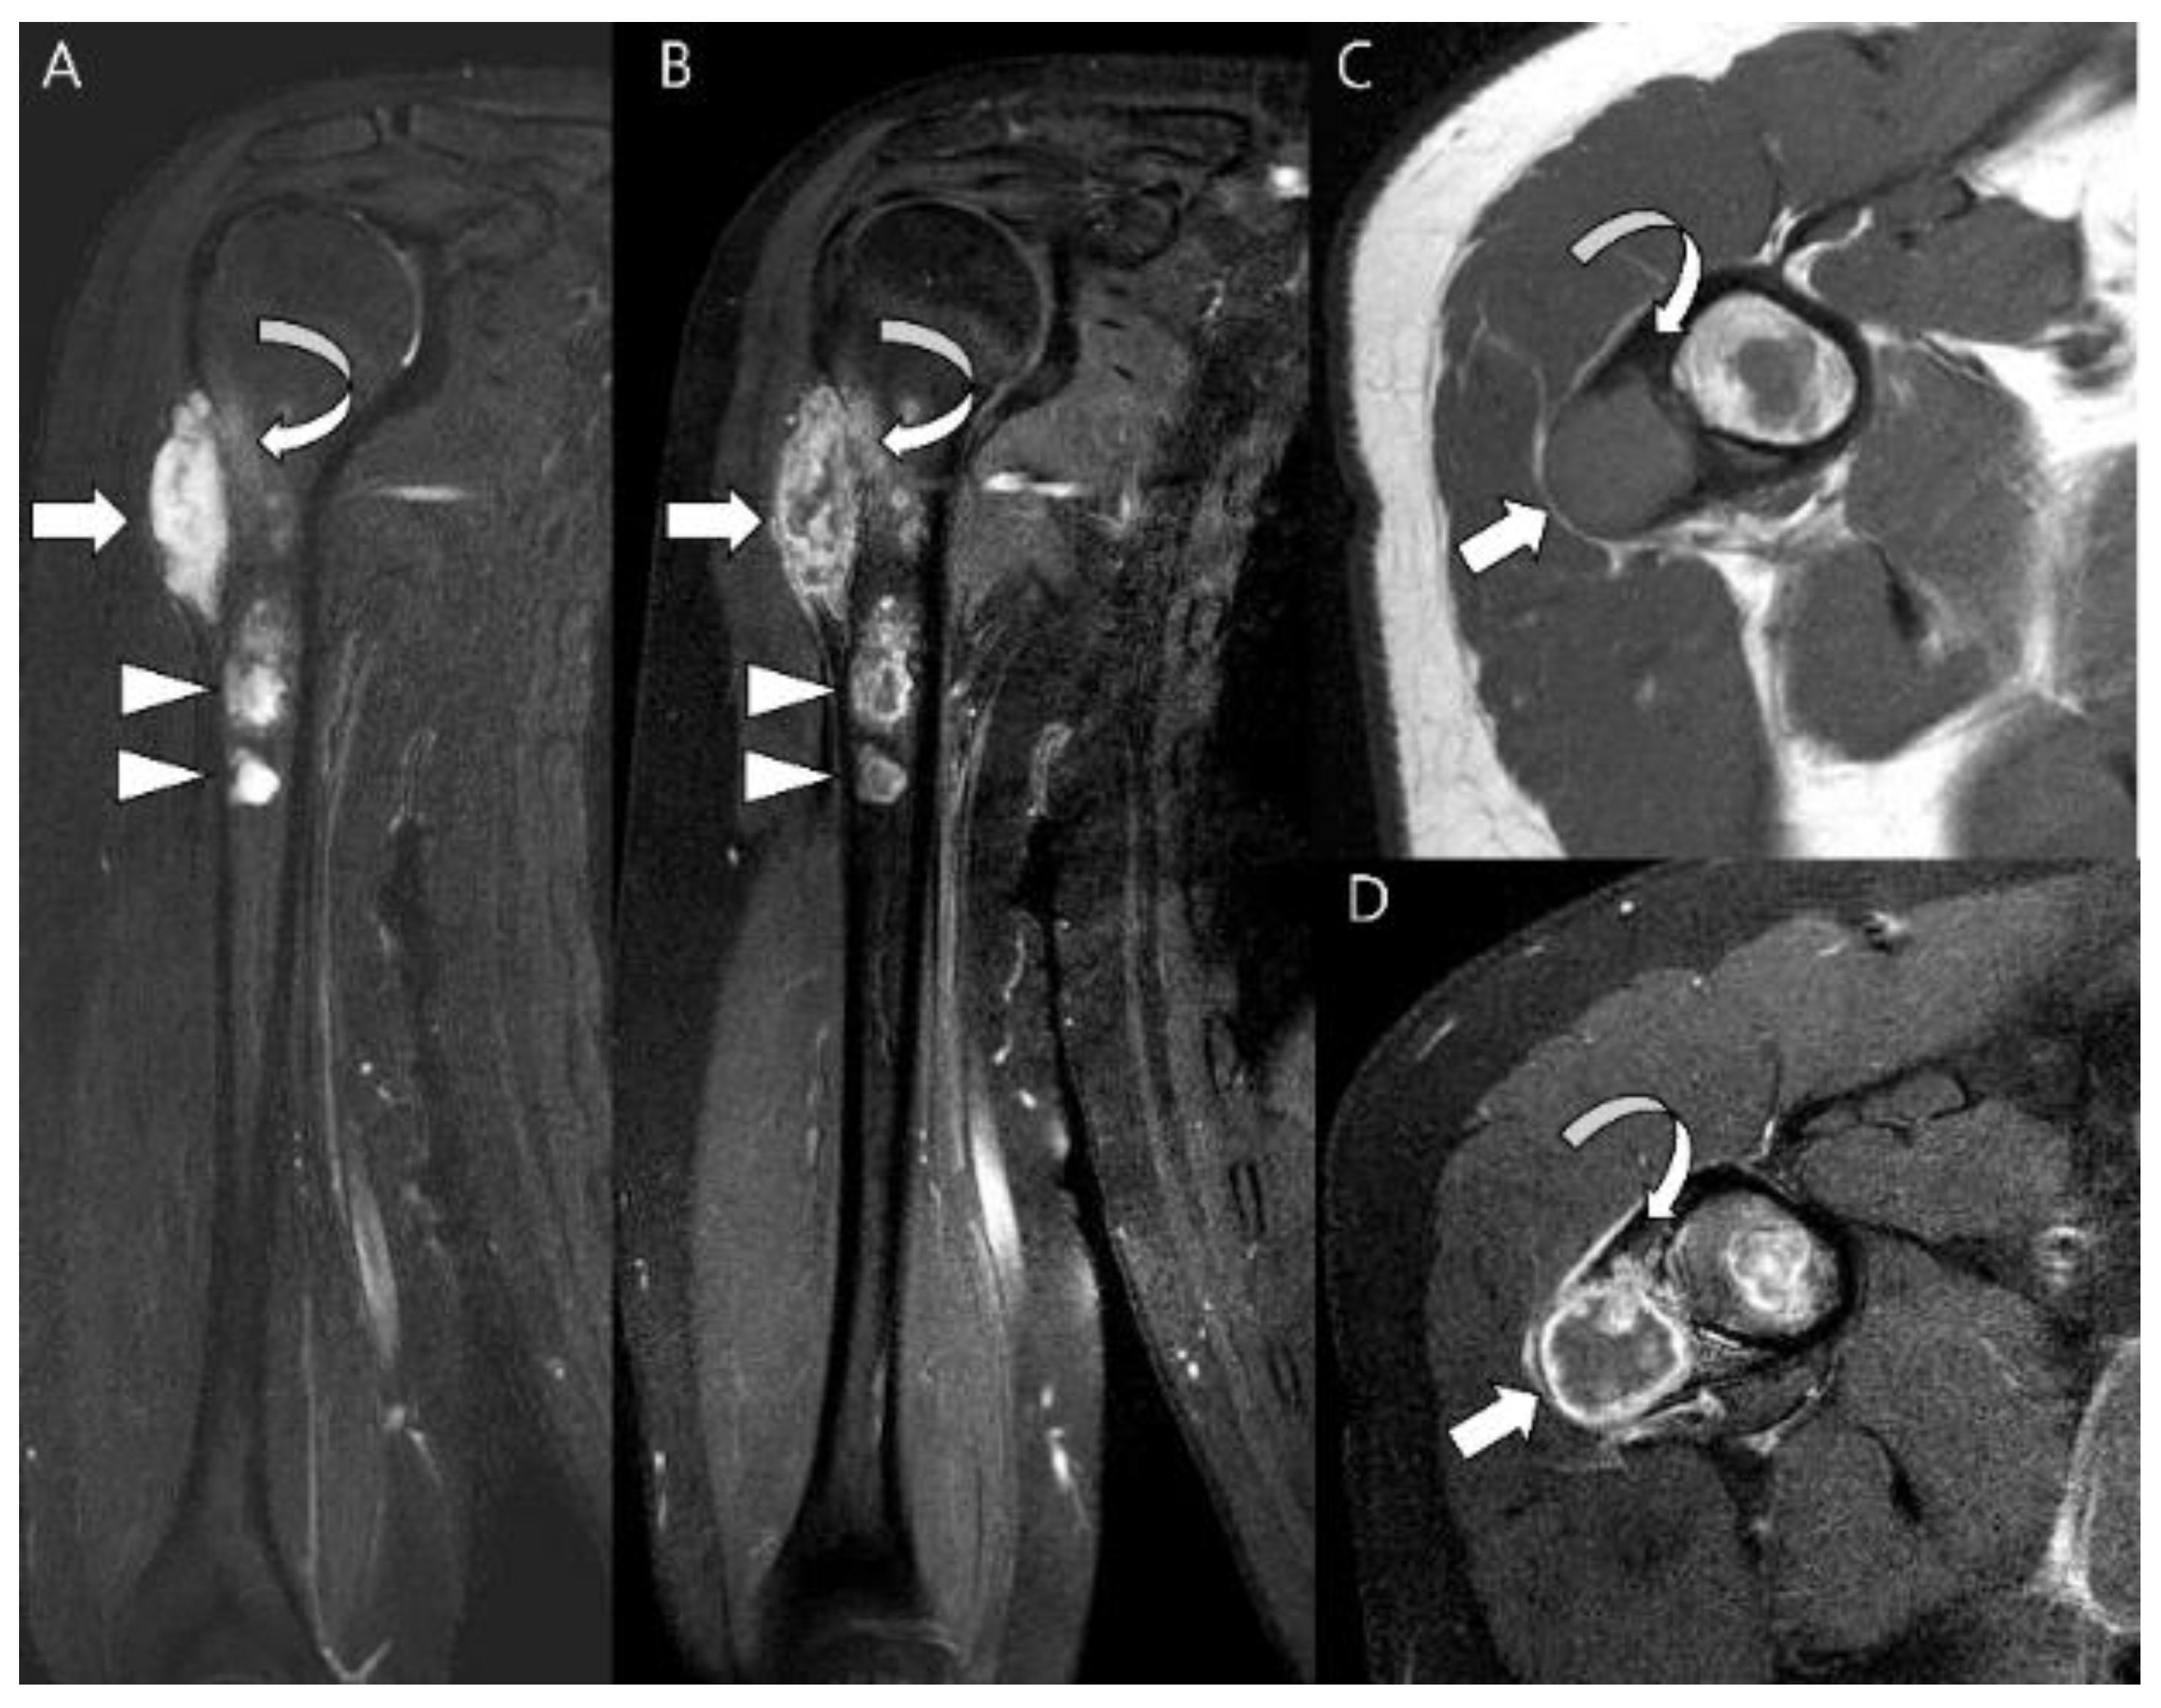

- Swanson, P.E.; Lillemoe, T.J.; Manivel, J.C.; Wick, M.R. Mesenchymal chondrosarcoma. An immunohistochemical study. Arch. Pathol. Lab. Med. 1990, 114, 943–948. [Google Scholar]

- Hoang, M.P.; Suarez, P.A.; Donner, L.R.; Ro, J.Y.; Ordñez, N.G.; Ayala, A.G.; Czerniak, B. Mesenchymal Chondrosarcoma: A Small Cell Neoplasm with Polyphenotypic Differentiation. Int. J. Surg. Pathol. 2000, 8, 291–301. [Google Scholar] [CrossRef]

- Nakashima, Y.; Unni, K.K.; Shives, T.C.; Swee, R.G.; Dahlin, D.C. Mesenchymal chondrosarcoma of bone and soft tissue. A review of 111 cases. Cancer 1986, 57, 2444–2453. [Google Scholar] [CrossRef] [PubMed]

- Ly, J.Q. Mesenchymal chondrosarcoma of the maxilla. AJR Am. J. Roentgenol. 2002, 179, 1077–1078. [Google Scholar] [CrossRef] [PubMed]

- Shinaver, C.N.; Mafee, M.F.; Choi, K.H. MRI of mesenchymal chondrosarcoma of the orbit: Case report and review of the literature. Neuroradiology 1997, 39, 296–301. [Google Scholar] [CrossRef] [PubMed]